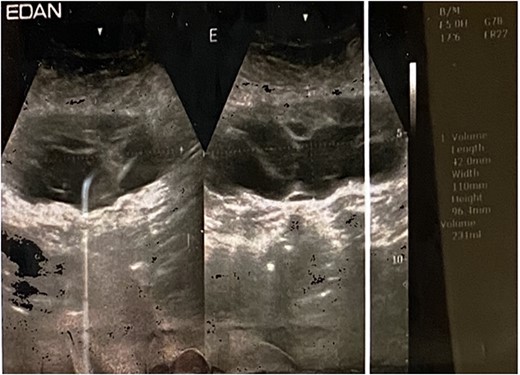

Non-postoperative early complications were found, drainage was removed on day 2 postoperative because it was not draining any fluid, and she was discharged home, with follow-up at day 8 postoperative where stitches were removed; on day 12 postoperative, she complained of surgical site pain and a fluctuant swelling was found on physical examination (Fig. 4); abdominal ultrasound confirmed seroma (Fig. 5). The decision to aspirate was based on the amount of fluid and the patient’s discomfort. 500 ml of serous-hematic fluid was aspirated. The patient is currently symptom-free.